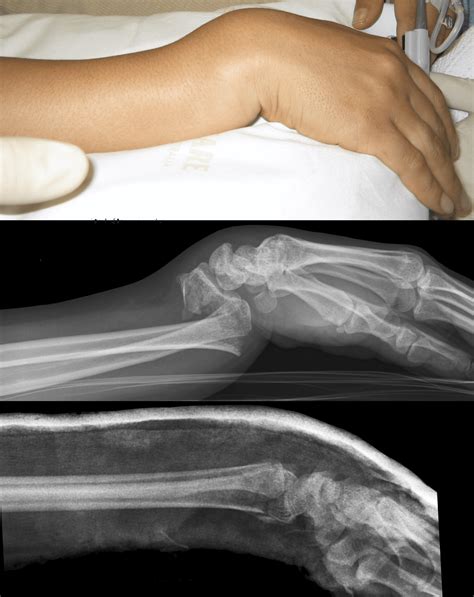

• Imaging Tests: X-rays, MRI, or CT scans to visualize the bone and surrounding tissues and confirm the diagnosis.

Case Study 1: A young athlete who experienced a subluxation of the radius during a sports injury. The athlete sought immediate medical attention and underwent a combination of rest, immobilization, and physical therapy. With proper treatment, the athlete was able to return to sports within a few months and has since maintained a healthy and active lifestyle.

Case Study 2: An individual with a congenital abnormality in the radius bone. This person experienced recurrent subluxations and sought surgical intervention to correct the underlying issue. Post-surgery, the individual underwent extensive physical therapy and has since reported significant improvement in joint stability and range of motion.